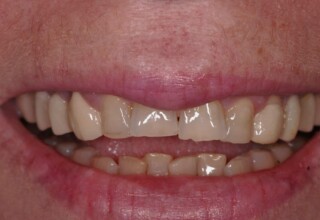

Composite Resin Veneers

Resin veneers are an inexpensive mode of esthetic improvement of anterior teeth, premolars also. Their potential is admirable and their limit is the operator’s clinical dexterity and imagination. In this case there were multiple problems with the upper four incisors: staining, poor inclinations, diastemas, multishading, poor interrelationship and poor tooth-gingiva ratios. They were restored with four direct composite resin veneers (one on a porcelain implant crown!) which were manufactured intraorally!!!